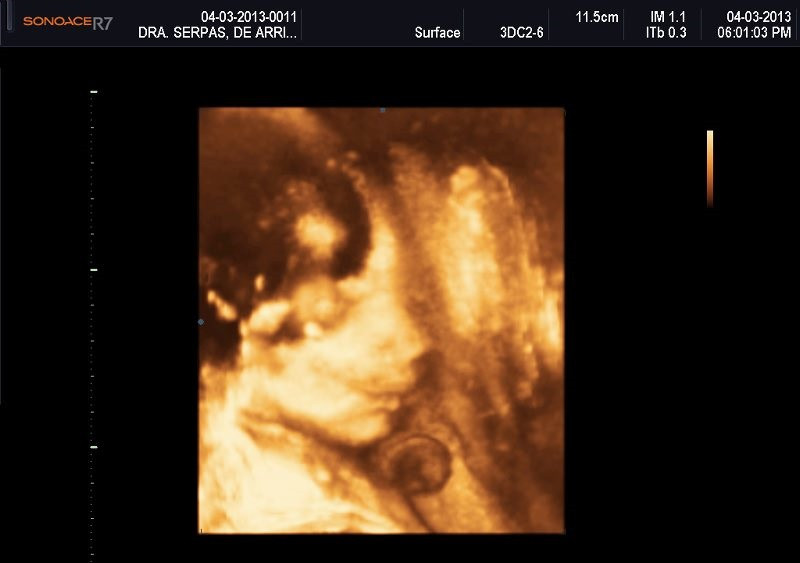

Varias ultrasonografías en 2D y 3D

Envíado por Dr. Nelson Menjívar Sarco